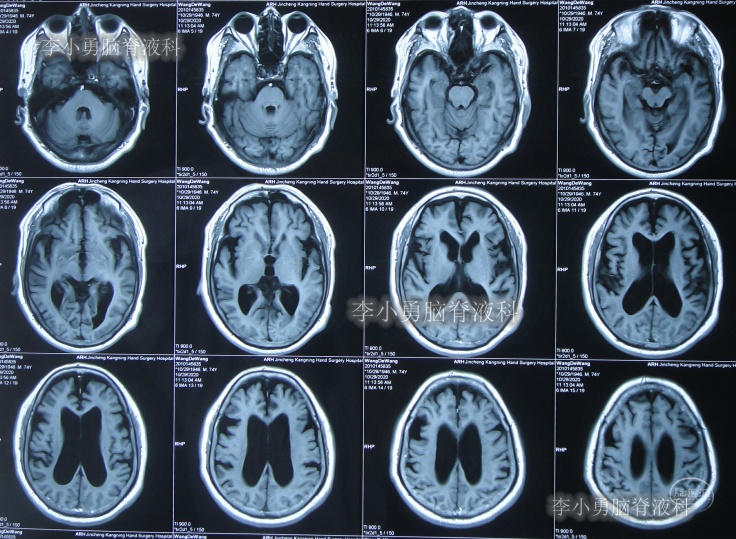

发现脑积水后8天即2020年11月6日,就诊于第2家的上海的某三甲医院,入院后再次检查(图-2)后诊断为正常压力脑积水。

图-2:2020年11月11日头部核磁